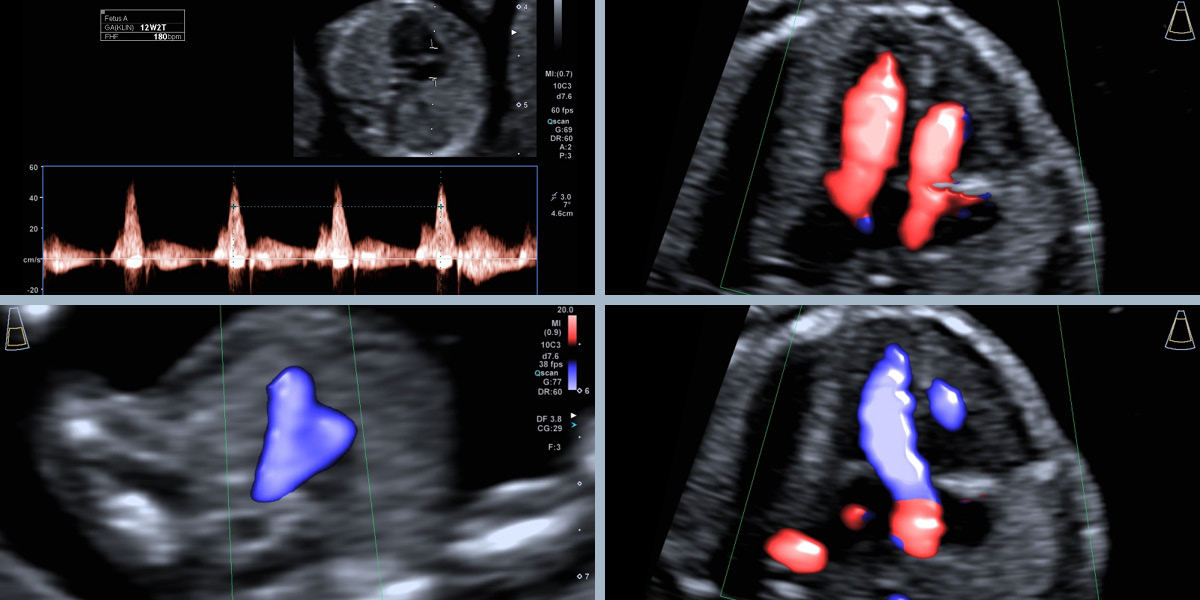

Das kindliche Herz zeigt normale Anatomie und unauffälliges Blutflussmuster.